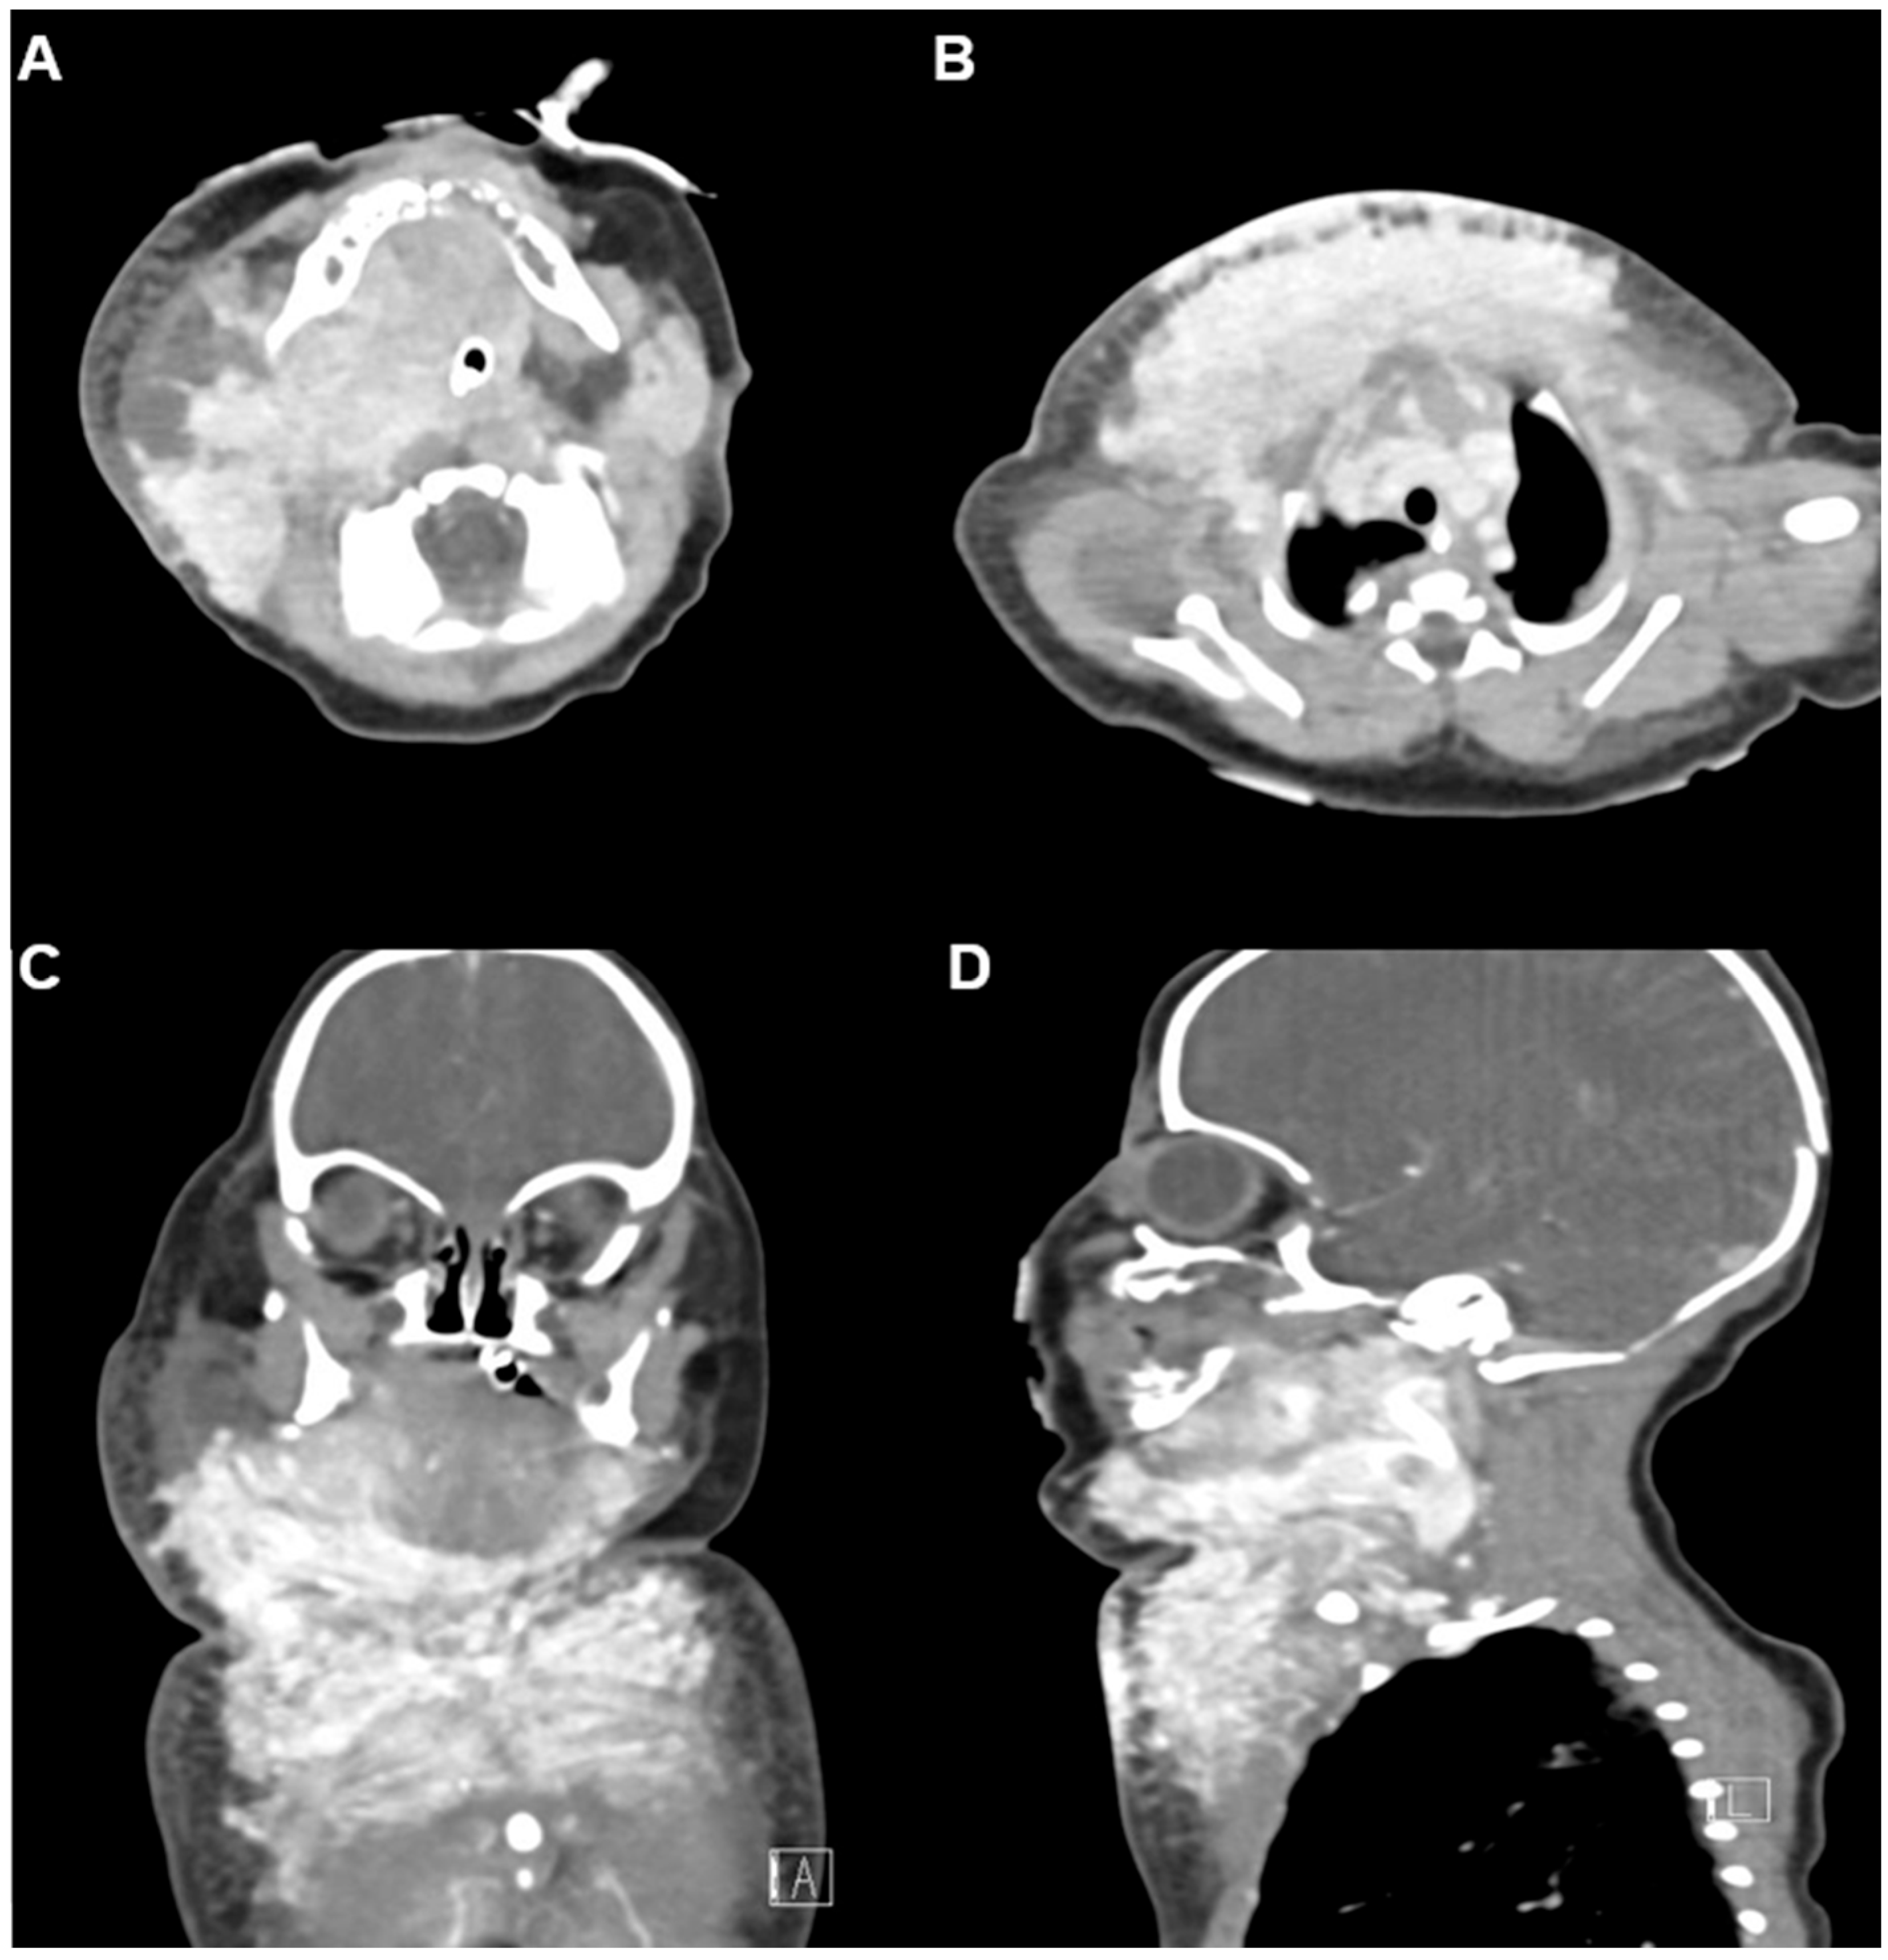

Neck and chest ultrasonography demonstrated a diffuse, infiltrative, and hypervascular soft tissue mass without cystic components. Contrast-enhanced CT performed at 5 days of life revealed an intensely enhancing infiltrative lesion involving the right parotid, submandibular, lingual, and retropharyngeal spaces, with extension into the posterior cervical compartments and both anterior deep soft tissue layers, further involving the upper anterior chest wall. The respiratory distress was considered to be due to external compression by the lesion rather than direct invasion of the upper airway. Numerous feeding and draining vessels were visualized (Figure 2A–D). These findings, together with the hematologic profile and clinical presentation, strongly supported a diagnosis of kaposiform hemangioendothelioma (KHE) complicated by Kasabach–Merritt phenomenon (KMP). Maternal-fetal antibody screening and immunologic workup were unremarkable, effectively excluding alloimmune thrombocytopenia and other hematologic disorders. Given the severe coagulopathy and associated high risk of hemorrhage, surgical biopsy was deemed unsafe, and a clinico-radiographic diagnosis was established.

Figure 2.

Initial contrast-enhanced CT at 5 days of age. (A,B) Axial and mediastinal views demonstrate an intensely enhancing infiltrative lesion involving the right parotid, submandibular, lingual, retropharyngeal, posterior cervical, and both anterior deep soft tissue layers, extending into the upper anterior chest wall. Numerous feeding and draining superficial and deep vessels are evident, consistent with a vascular tumor. Endotracheal tube is in situ. (C) Coronal and (D) sagittal views further delineate the mass with associated subsegmental atelectasis in the left lower lobe.